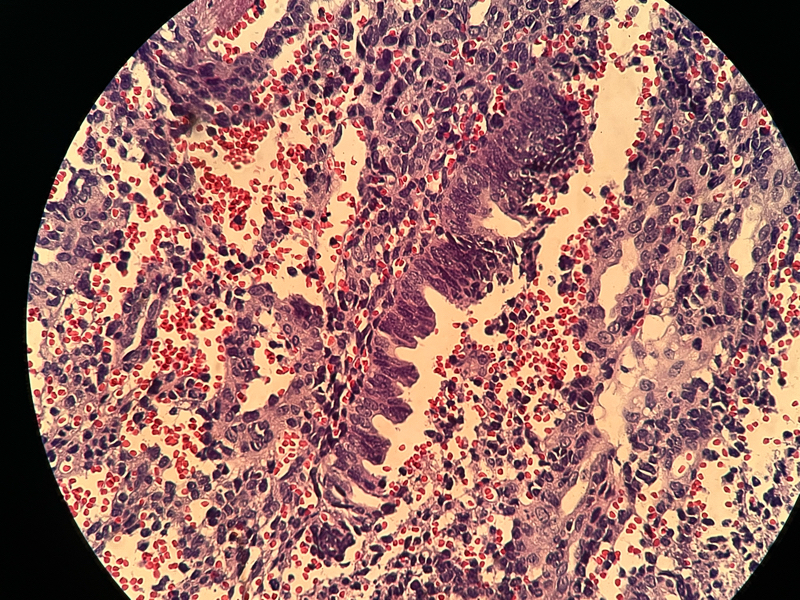

宫内膜组织

性别

女

年龄

37

临床诊断

功血

一般病史

阴道不规则流血20天

标本名称

大体所见

灰白灰红膜样物质一堆,约2.1✖️1.2✖️0.4

图1

倾向内膜息肉

组织形态符合子宫内膜息肉,表面有乳头的那些区域要鉴别乳头样化生和表面浆液性肿瘤,免疫组化可能会有帮助。